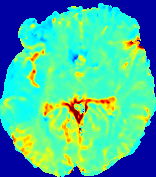

4.3.1 Advection Imaging via Advection-Diffusion

Slice #1Slice #2Slice #3Slice #4Slice #5Slice #6𝐕gt𝟐subscriptnormsuperscript𝐕gt2\|\bf{V}^{\text{gt}}\|_{2}Refer to captionRefer to captionRefer to captionRefer to captionRefer to captionRefer to caption𝐕est𝟐subscriptnormsuperscript𝐕est2\|\bf{V}^{\text{est}}\|_{2}Refer to captionRefer to captionRefer to captionRefer to captionRefer to captionRefer to captionRefer to caption1.51.51.51.21.21.20.90.90.90.60.60.60.30.30.30.00.00.0(mm/s)𝑚𝑚𝑠(mm/s)Destsuperscript𝐷estD^{\text{est}}Refer to captionRefer to captionRefer to captionRefer to captionRefer to captionRefer to captionRefer to caption0.0150.0150.0150.0120.0120.0120.0090.0090.0090.0060.0060.0060.0030.0030.0030.0000.0000.000(mm2/s)𝑚superscript𝑚2𝑠(mm^{2}/s)

Figure 14: PIANO identifiability testing: advection imaging via advection-diffusion. Top row shows 𝐕gt2subscriptnormsuperscript𝐕gt2\|{\bf{V}}^{\text{gt}}\|_{2} used for simulating ground truth pure advection. Rows below show the estimated 𝐕est2subscriptnormsuperscript𝐕est2\|{\bf{V}}^{\text{est}}\|_{2} and Destsuperscript𝐷estD^{\text{est}} on corresponding slices. Note that the plotted value scale for Destsuperscript𝐷estD^{\text{est}} is 0.01 of that for 𝐕gt2subscriptnormsuperscript𝐕gt2\|{\bf{V}}^{\text{gt}}\|_{2} and 𝐕est2subscriptnormsuperscript𝐕est2\|{\bf{V}}^{\text{est}}\|_{2}.

We use the same ‘Advection Imaging’ simulation of Sec. 4.2.1 as the concentration dataset for PIANO. However, instead of modeling pure advection (Eq. 15), we let PIANO estimate both velocity 𝐕estsuperscript𝐕est{\bf{V}}^{\text{est}} and diffusivity Destsuperscript𝐷estD^{\text{est}} via the advection-diffusion PDE (Eq. 2) underlying the proposed PIANO model. Fig. 14 shows the estimated 𝐕est2,subscriptnormsuperscript𝐕est2\|{\bf{V}}^{\text{est}}\|_{2}, and Destsuperscript𝐷estD^{\text{est}} fields for one patient. Although PIANO has the freedom to estimate both a velocity and a diffusivity field from pure advection, PIANO differentiates well between advection and diffusion: the estimated 𝐕est2subscriptnormsuperscript𝐕est2\|{\bf{V}}^{\text{est}}\|_{2} successfully reproduces the ground truth 𝐕gt2subscriptnormsuperscript𝐕gt2\|{\bf{V}}^{\text{gt}}\|_{2} governing the simulated advection process, just as it already did in the ‘Advection Imaging via Advection’ test (Fig. 12). More importantly, the estimated diffusivity Destsuperscript𝐷estD^{\text{est}} is orders of magnitudes smaller than 𝐕est2subscriptnormsuperscript𝐕est2\|{\bf{V}}^{\text{est}}\|_{2}, indicating the estimated diffusion is negligible compared to the estimated advection, which is highly consistent with the underlying pure advection of the simulated data.